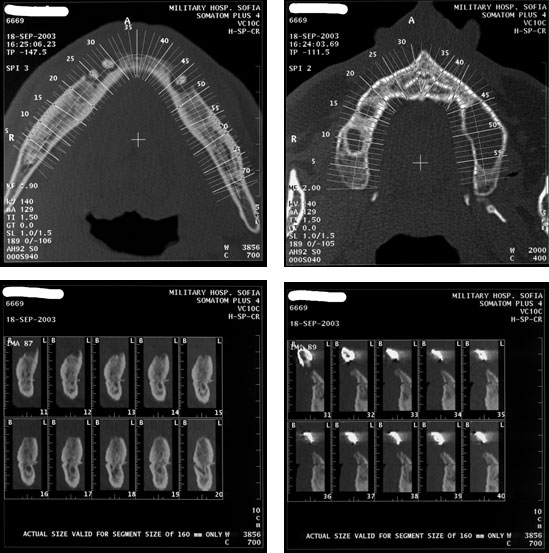

[/userfiles/files/mlt9.jpg]Съвременните компютърни томографи /скенери/ дават триизмерен образ на разрези на челюстта на всеки 2 мм., което твърде много улеснява работата на имплантолога.

[/userfiles/files/mlt11.jpg]Ето така изглежда скенерът на долната челюст на 45 годишна пациентка, по професия балерина, страстен пушач.

[/userfiles/files/mlt12.jpg]На показаните срезове се вижда съвсем тънка алвеоларна кост, където, след прерязване на острите върхове можеха да се поставят само имплантати MTI, чийто диаметър бе 1.8 мм.

В областта на срез № 18, срезове № 35 и 39, отговарящи съответно на 36,37 и 46-ти зъби, бяха поставени имплантати T.B.R.